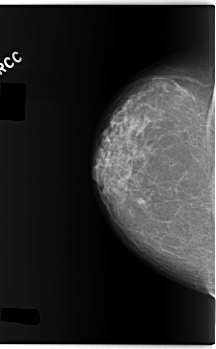

C_0275_1.LEFT_CC

LEFT_CC LINES 5968 PIXELS_PER_LINE 3576 BITS_PER_PIXEL 12 RESOLUTION 50 NON_OVERLAY